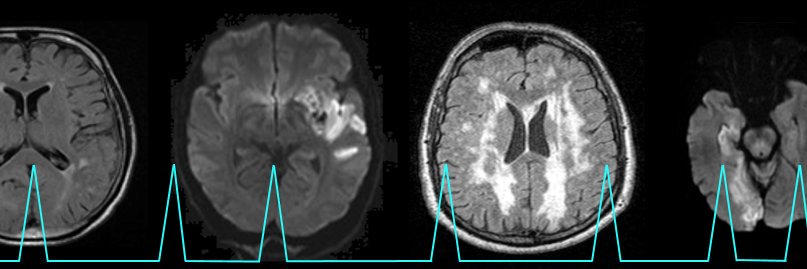

A coalition of neurologists dedicated to better understanding stroke development and improving stroke prevention in patients with atrial fibrillation.

Drs. Greenberg, Gurol and Kharal gearing up for our fourth and final session of this year’s #NeuroAFib Investigator Meeting! 🧠